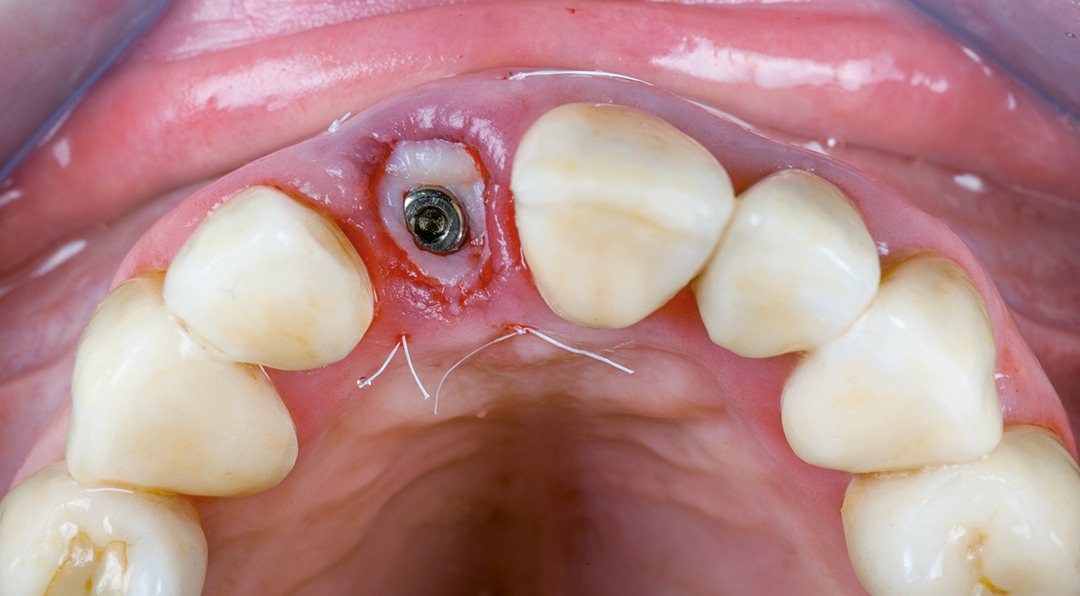

Surgery and initial outcomes

The remaining root was carefully and atraumatically extracted using a Benex® pull-out device. The surgical guide was fitted in the mouth and a CONELOG PROGRESSIVE-LINE implant with conical connection was immediately placed, torqued to above 50 Ncm for high primary stability. The space between the implant and the facial cortical bone plate was filled with MinerOss XP biomaterial and a connective tissue graft was tunnelled around the neck of the implant. This was harvested from the tuberosity, de-epithelialised, and added around the neck of the implant. The objective of this procedure was to ensure long-term papilla stability and prevent both the future collapse of the soft tissue and opening of the embrasures. This is paramount when restoring a gap in the anterior zone.

A scanbody was used to register the implant position and a provisional restoration was designed in exocad software and milled in PMMA. The temporary restoration would be used to help stabilise the connective tissue graft, while also shaping the soft tissues to develop a good emergence profile. This is an important transition stage before the final restoration.